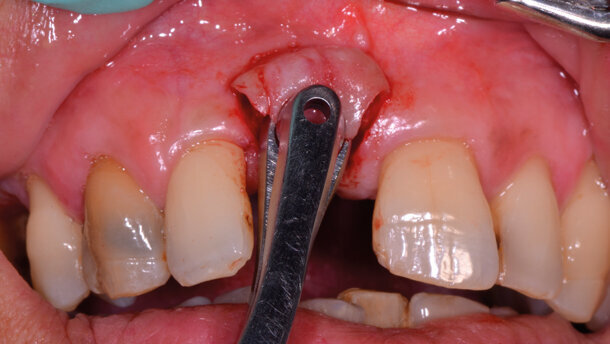

Dopo un’accurata anamnesi e un esame radiologico ortopantomografico ed endorale, abbiamo programmato l’intervento di implantologia osteointegrata, escludendo l’eventualità di una terapia di rigenerazione ossea contestuale e di supporto al suddetto intervento, a causa del veto della paziente a sottoporsi a tale terapia rigenerativa. Infatti alla paziente era stato proposto una chirurgia muco-gengivale parodontale alfine di incrementare sia la qualità che la quantità dei tessuti molli perimplantari, mediante un intervento di tessuto connettivo prelevato dal palato. Per aumentare il comfort della paziente abbiamo eseguito l’anestesia con tecnica computerizzata indolore STA ed esposto il tessuto osseo sottostante attraverso un lembo muco-periosteo a spessore totale, con un’incisione crestale senza incisioni di rilascio. Avvalendoci di una sonda parodontale, ortogonale alle superfici vestibolari degli elementi contigui, abbiamo preparato il letto implantare rispettando i canoni protesici ed estetici (Figg. b, c). L’impianto BTK BT-Konic in titanio con superficie DAES (double acid etched surface) è stato inserito avvalendoci del contrangolo implantare e finalizzato manualmente con cricchetto dinamometrico a 50 N/cm. Il mounter usato per l’inserimento è stato poi smontato e inserita la vite tappo (Figg. d, e). Infine, abbiamo suturato il lembo allestito con sutura in seta 4/0. A distanza di 3 mesi, nella fase di rientro implantare per la finalizzazione protesica, è stato effettuato un lembo trapezioidale con incisione paracrestale, per ottenere nella fase di guarigione un aumento della quantità di gengiva aderente indispensabile per ottenere un sigillo implanto-protesico, viene dunque inserita la vite di guarigione di altezza e diametro idonei a garantire una corretta cuffia gengivale (Figg. f, g). Prima di dimettere la paziente, abbiamo eseguito un esame radiografico endorale di controllo. A distanza di 6 mesi dall’inserimento implantare, abbiamo svitato la vite di guarigione e protesizzato l’impianto con un abutment personalizzato e relativa corona in metallo-ceramica con aggiunta di ceramica rosa a livello del colletto per evitare l’ effetto inestetico di “dente allungato” (Fig. h).